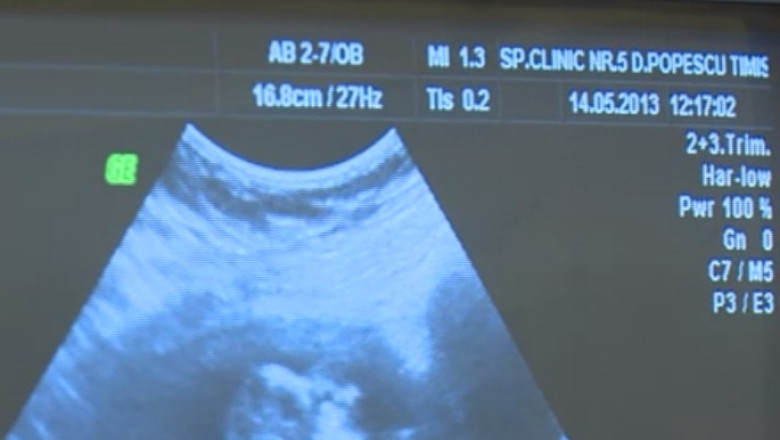

TIMISOARA. Specialisti din cinci tari ofera consultatii gratuite cu un ecograf performant

Pacientele vor fi consultate patru ore pe zi, de astăzi, până miercuri. Fiecare consultație durează maximum o jumătate de oră. În prezent, peste 10% dintre gravide au probleme cu sarcina, însă, depistate la timp, ar putea fi tratate.

Tot în această perioadă, specialiştii din străinătate vor susține şi sesiuni de training pentru medicii din Timişoara. Acţiunea face parte dintr-un proiect transfrontalier, în valoare de două milioane de euro. Prin intermediul acestuia, şi Timişoara va avea un astfel de ecograf, cel mai probabil la mijlocul anului viitor.